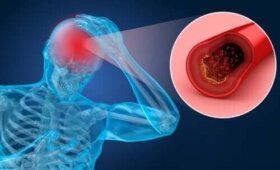

뇌졸중의 위험 요인 및 증상에 대해 알아보자. 이 병은 위험 요인이 많으며 증상도 다양한 갑작스럽게 생기는 신경 증후군이다. 뇌의 출혈이나 혈액 순환이 안 되는 증상과 연관된다. 뇌에 혈액이 제대로 공급되지 않으면 뇌 조직은 파괴된다. 이렇게 되면 장애나 심지어 사망으로 이어질…